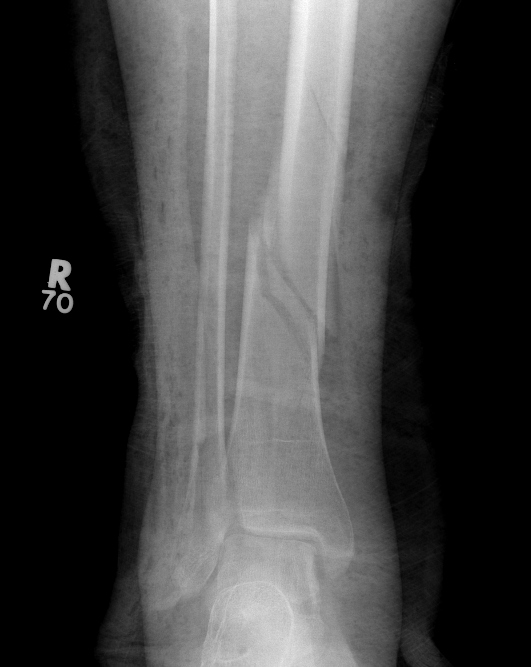

Posterior Malleolar Fractures

- occult in 70%

- especially with spiral distal tibial fractures